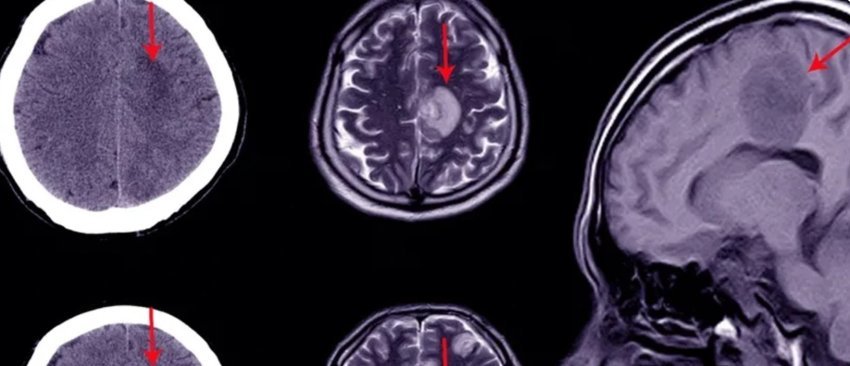

Gjakderdhja në tru është e shpeshtë, sidomos te të moshuarit – rikthimi mbetet problem serioz

Hematoma subdurale subakute dhe kronike janë të shpeshta, veçanërisht te personat e moshuar. Edhe pas heqjes kirurgjikale, e cila pritet të bëhet procedura neurokirurgjikale kraniale më e shpeshtë deri në vitin 2030, sëmundja rikthehet te 8–20% e pacientëve.